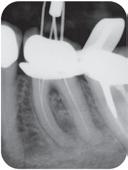

Høykonsentrert tyntflytende kalsiumhydroksidpasta med >41% hydroksid i en konsistens som enkelt appliseres med en liten og fleksibel plastkanyle: Flexi-Tip. Autoklavérbare Flexi-Tip i kombinasjon med den myke konsistensen sparer deg for tid, og hjelper deg å oppnå en presis og dyp applisering. pH 12,4 gjør den baktericid. Langvarig. Røntgenkontrast. 589,-

Høykonsentrert kalsiumhydroksid på >41%. pH 12,4 gir høy antibakteriell effekt, bakteriedrepende. Røntgenkontrast. Langvarig. Klar til bruk, appliseres direkte gjennom steril kanyle.

Calasept EDTA

Skyllevæske til kjemisk utvidelse av rotkanaler. Letter den mekaniske utrenskningen. Leveres med adapter til skyllesprøyten. Nå 250ml.

2% Klorhexidindiglukonat. Benyttes etter EDTA ved revisjonsbehandlinger og alle typer nekrosebehandlinger. Nå 250ml.